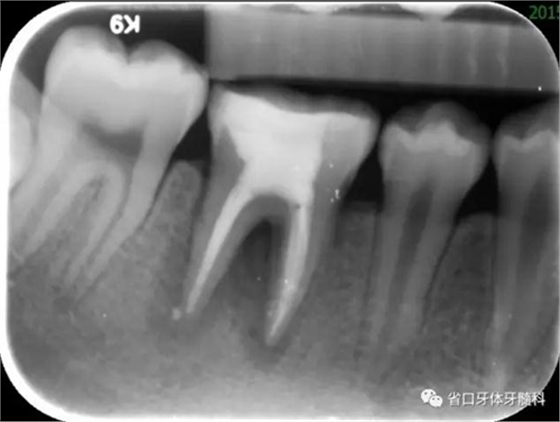

圖2 根管治療術后即刻X線片